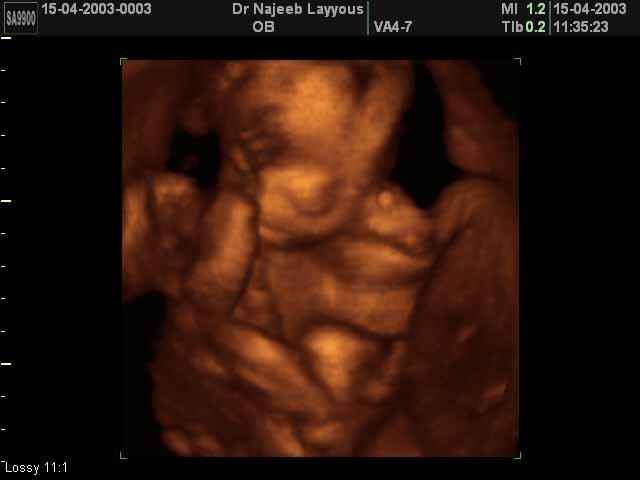

- تصرفات الجنين داخل الرحم

- صور لتصرفات الجنين داخل الرحم

صور لتصرفات الجنين داخل الرحم بجهاز الالتراساوند ثلاثي الأبعاد | الدكتور نجيب ليوس